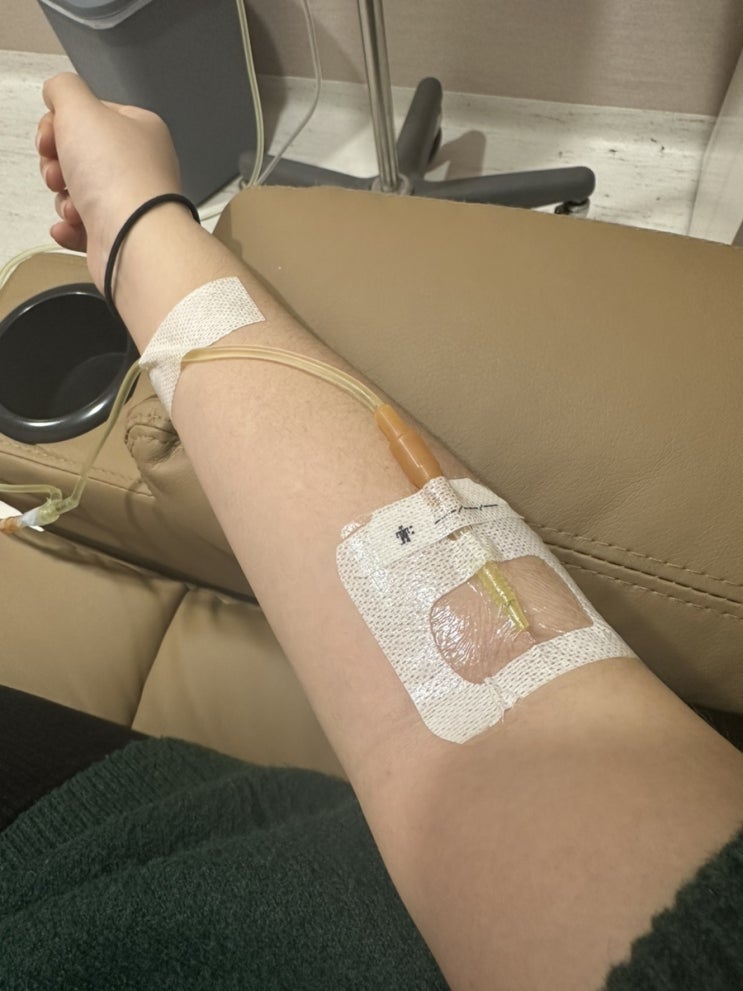

21~22주 쌍둥이 태아보험 가입 후기(+꿀팁, 가입시기, 불필요한 특약)

21주 목주름이 너무 많이 생겼다ㅜㅜ 배는 점점 불러오는데 위도 불편해서 계속 높은 베개를 배고 잔 탓일...